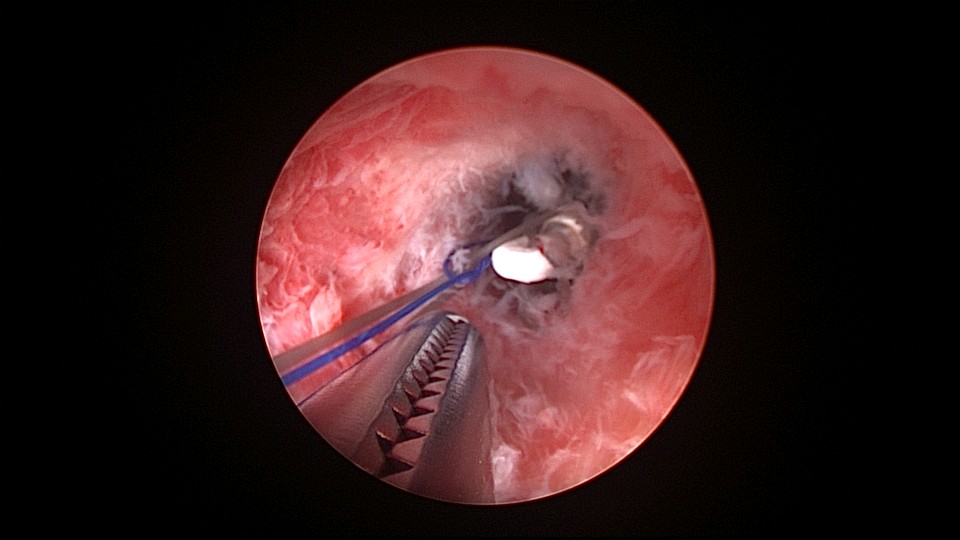

患者38岁,G2P1,剖宫产1次。安环13年,发现内膜息肉3年伴月经淋漓不净。2025年3月行宫腔镜取环、息肉切除,同时放置曼月乐环并固定。子宫后位,宫深7.5cm,宫型环位置正常,宫颈管及宫腔后壁见息肉,顺利取出节育环,切除息肉送病检,4-0不可吸收线将曼月乐缝合固定于宫腔上段后壁,第一次做宫腔镜下缝合固定节育环,体外打结后推结到位比较困难,今后改进缝合固定方式。病检为子宫内膜息肉及增殖期子宫内膜。2025年4月复查B超,曼月乐位置正常,环顶端距宫底1.3cm。